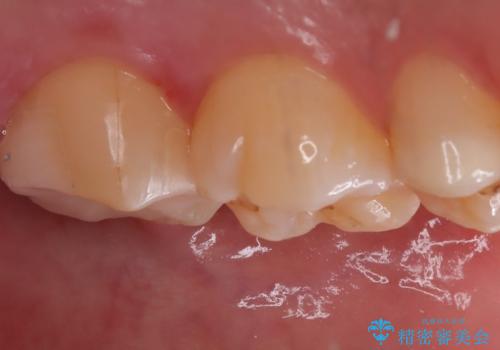

- 主訴:左上の銀の詰め物、笑うと見えそうで気になるので白くしたい。

保険適応のメタルインレーが入っていたため、適合性・審美性の良いセラミックインレーでのやり替えとなりました。

保険適用のメタルインレーを除去したところ、歯質との境目部分にカリエスを認めたため、カリエス除去しCR裏層の後、セラミックインレーを形成しました。